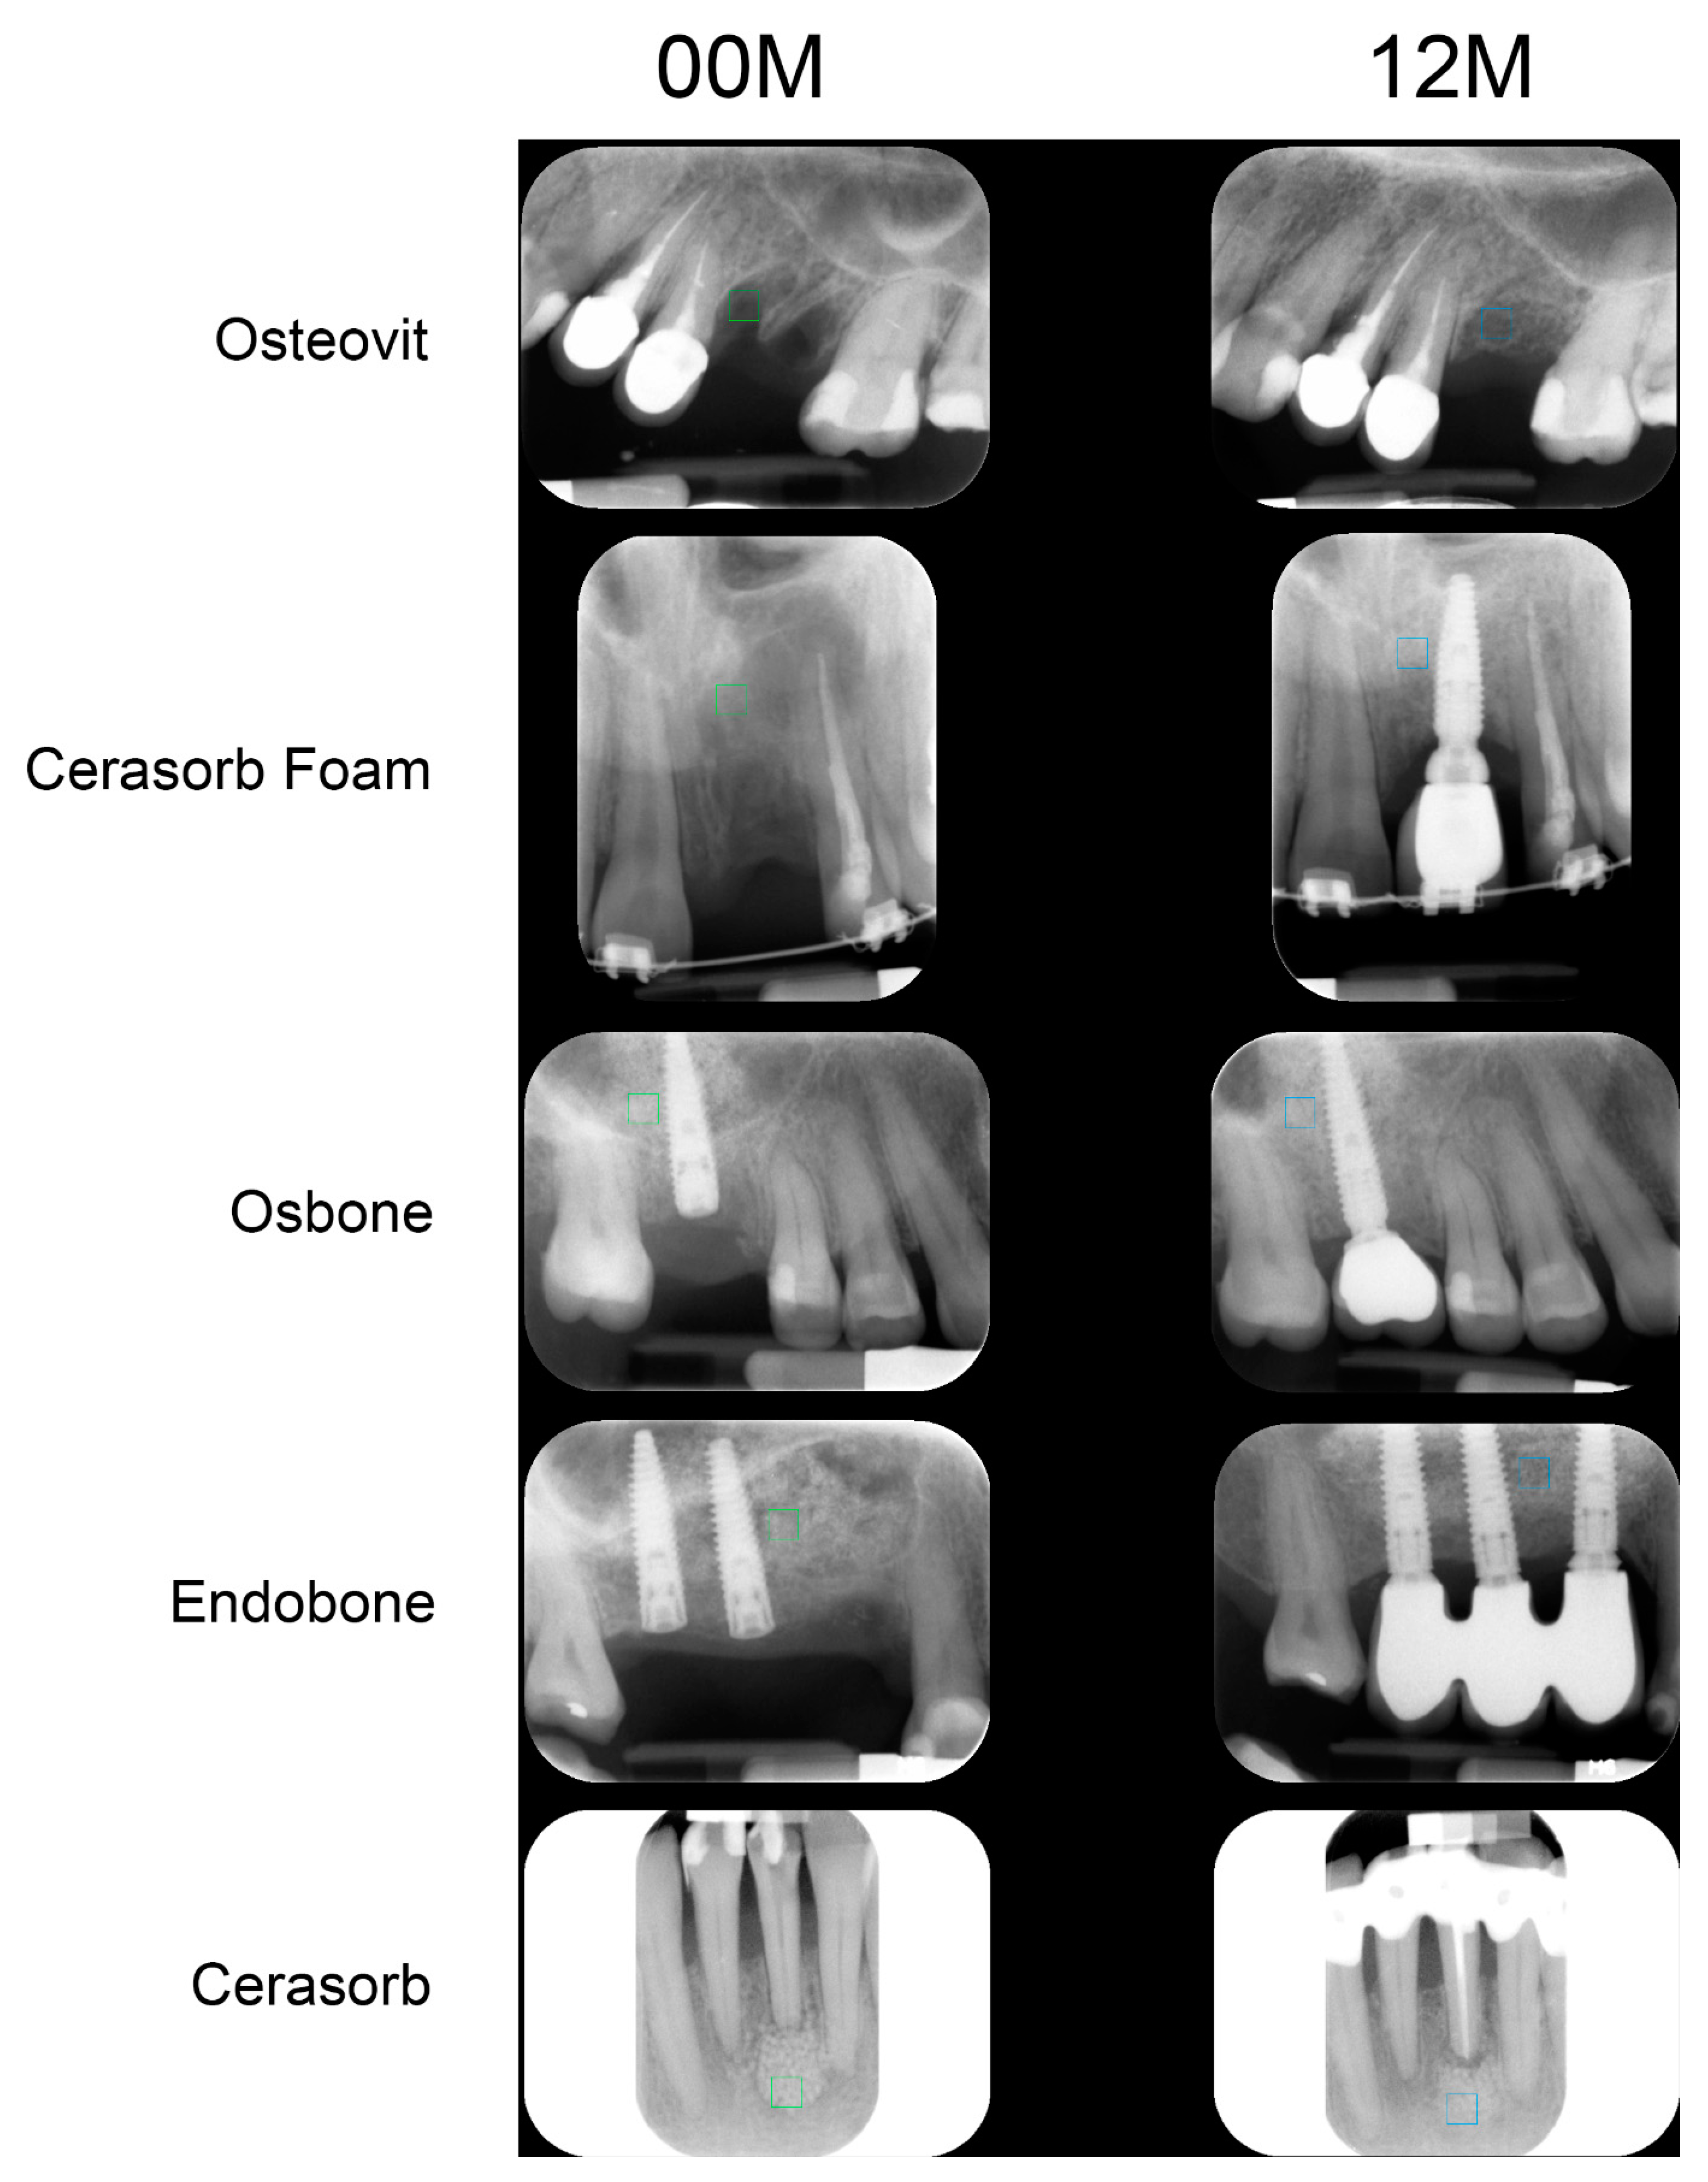

New Oral Surgery Materials for Bone Reconstruction—A Comparison of Five Bone Substitute Materials for Dentoalveolar Augmentation

2. Materials and Methods

3. Results